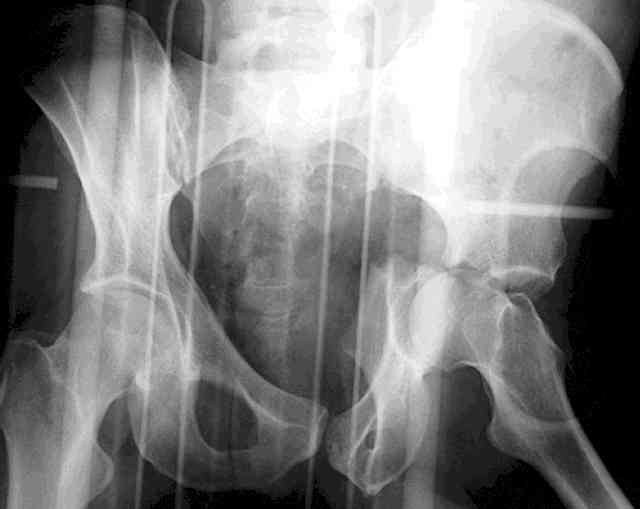

The 2nd example is of a motorcyclist with a transverse fracture-dislocation...he had a closed attempted reduction and placed in traction but the manipulative reduction was not concentric (not unusual for this injury pattern)...so the traction was adjusted to be just enough to disengage the head from the fracture (12#) until he could be cleared for surgery one day after injury...he was treated "urgently" then with a prone KL, clean the fracture, reduce and clamp it, screw it, support with a balanced plate, close, and enjoy...2-3hours, 400cc EBL, blah, blah, blah..